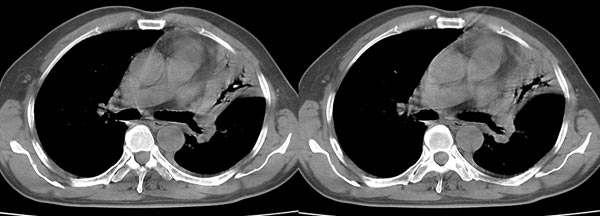

以下是引用dyqct在2006-4-1 22:20:00的发言:[br]左肺上叶明显萎陷、实变,支气管大部通畅,部分扩张,部分壁似见串珠状钙化。主动脉弓旁见肿大淋巴结。纵隔左移。左侧胸壁后缘见新月形高密度,边界清楚。[br] 考虑:1、左肺上叶肺不张伴支气管扩张(牵拉性),可能为支气管内膜结核所致。[br] 2、左侧少量胸腔积液。[br]

以下是引用piao001在2006-4-2 14:13:00的发言:[br]左肺上叶不全性不张,其内见钙化及扩张支气管,结合病史,考虑支气管内膜结核。建议支气管镜明确检查。